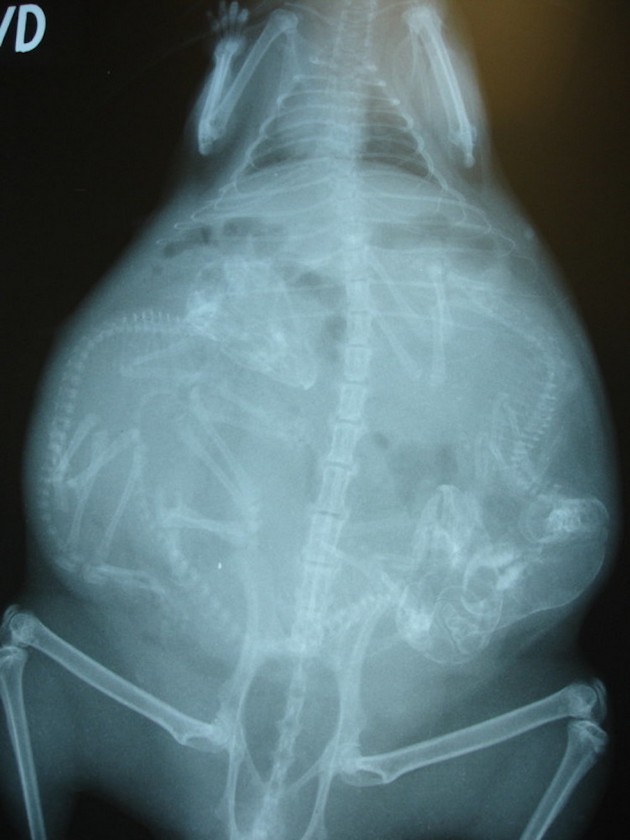

Radostné očakávanie môže u rôznych zvieracích druhov vyzerať všelijako. Fotky, ktoré vám dnes ukážeme sú raritné a rozhodne zaujímavé. Predsa len, videli ste už niekedy tehotné zvieratá cez röntgenové snímky?

Niektoré z nich rodia živé mláďatá, iné zasa kladú vajíčka. Zrod nového života vo zvieracej ríši je každopádne fascinujúci. A ako vyzerajú tehotné zvieratká sa môžete pozrieť na nasledujúcich “lekárskych” snímkoch.

Činčila